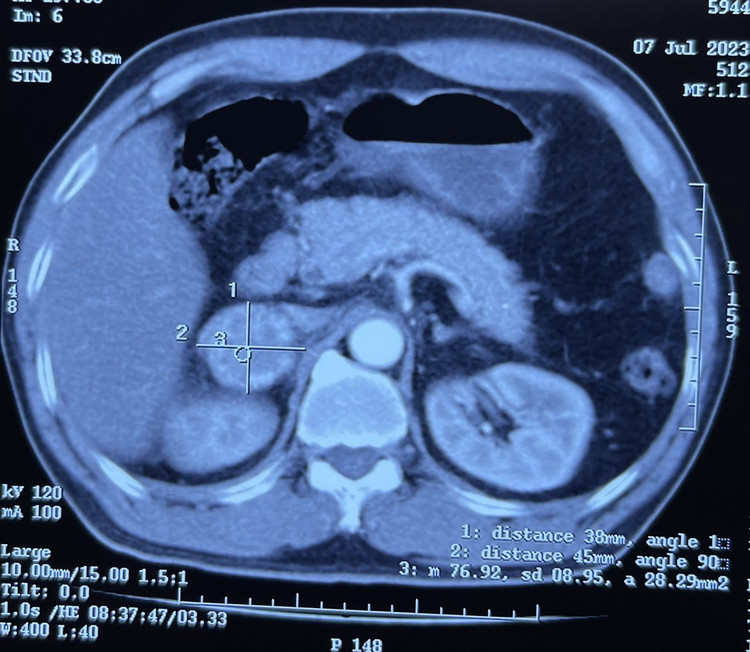

Khối u trên phim chụp cắt lớp vi tính) |

Khối u trên phim chụp cắt lớp vi tính)